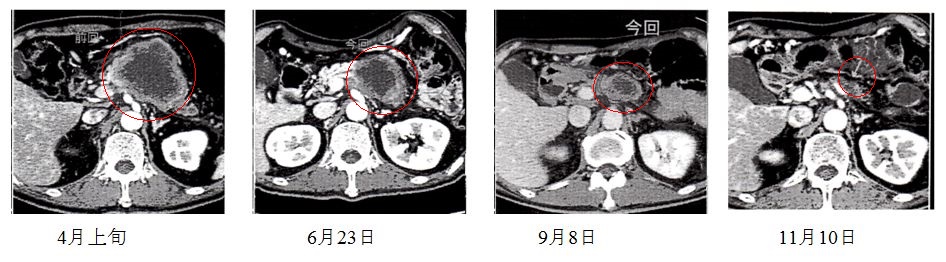

平成27年年4月上旬、胃の痛みがあったので病院に受診、1週間後検査結果がステージⅣの末期、8cmから10cm大のすい臓がんが血管に巻き付いて

いるので手術で取り除くことが不可能と診断されました。

て、6月23日ガンマーカー10が7まで下がり腫瘍が約3分の1まで縮小し、9月の検査でも縮小、11月10日CTの検査にて、すい臓がんが米粒大まで縮小、半信半疑で抗がん剤と併用したサプリとインドの博士の論文が嘘ではなかったことに喜びを感じました。

12月2日、掛かりつけの医師より、癌が米粒大になっていることを知らされ、先生の話では、すい臓がんがここまで縮小する例は初め

て見たと言っておらました。